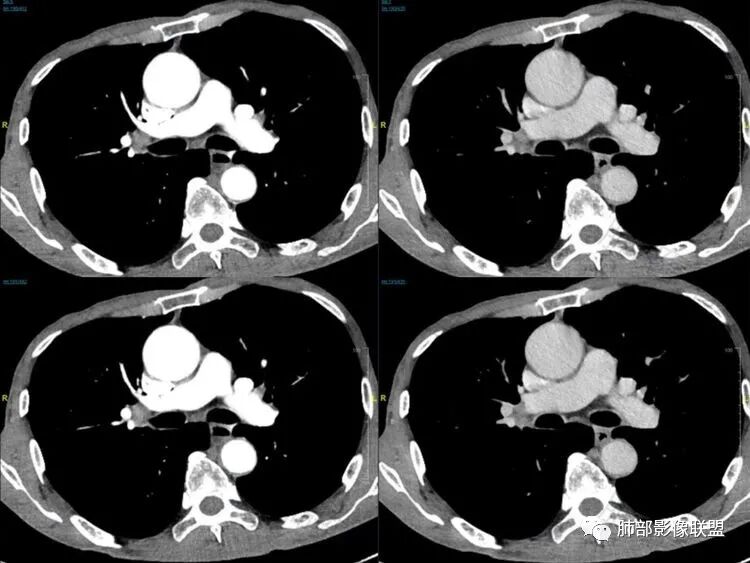

老年男性患者,胸部隐痛1月入院,有长期吸烟史,胸部CT:右肺下叶背段梭型结节灶,边界清晰,无明显分叶、毛刺及周边磨玻璃影,内部密度不均匀,支气管截断,增强扫描不均匀轻度强化,内部似乎见支气管黏液栓,纵隔淋巴结不大,考虑恶性病变:小细胞癌(缺少典型的纵隔肺门淋巴结增大融合),鳞癌(病史复合,但没有阻塞性肺炎,内部没有坏死,),类癌(多见于女性患者,与吸烟关系不大),首先考虑典型类癌,

老年男性,右肺下叶梭形或椭圆形结节,形态较规则,边缘光整,支气管截断,增强不均匀轻度强化,右肺门及纵隔淋巴结增大,考虑恶性病变,鳞癌或小细胞癌,神经内分泌癌(小细胞形)。

老年男性患者,右肺下叶背段梭形结节影,边界比较光整,密度均匀,没有明显的分叶毛刺,没有阻塞性肺炎的表现,这些感觉具备有良性的特点。而近端支气管截断,增强明显的强化,纵隔多发的淋巴结,显得是恶性的特点。总体印象,老年患者+支气管截断征象+明显强化的结节+纵隔多发淋巴结,还是考虑恶性结节,小细胞癌或是鳞癌。

男性,老年人,长期吸烟史,老慢支背景,右下肺背段占位,支气管亚段门口堵,病灶长轴与支气管平行,推测腔内生长可能,病灶内血管穿行,周围干净,轻度强化,右肺门淋巴结肿大,考虑恶性,神经内分泌癌(大小类)>淋巴上皮瘤样癌>腺癌>鳞癌

右肺下叶梭形实性结节,密度均匀,边缘光整,局部膨隆,近端支气管截断,轻度强化,血管走行自然,右肺门及纵隔淋巴结增大,考虑小细胞癌>鳞癌

右肺下叶背段结节,沿着支气管走行呈长椭圆形,边缘圆滑清晰,近端支气管阻塞,远端支气管有沿壁增厚,右肺门淋巴结肿大,中度强化,老年男性,吸烟病史,肺气肿背景,考虑小细胞肺癌,鉴别鳞癌

老年男性,吸烟史,右肺下叶梭形肿块,边缘平直有分叶,支气管近端阻塞,右肺门肿大淋巴结,增强后轻度强化,欠均匀,首先考虑恶性,小细胞肺癌?

老年男性,吸烟史,右肺下叶背段梭型软组织肿块,边缘膨隆,不均匀强化,近端支气管截断,同侧肺门及纵隔淋巴结肿大,支持恶性,小细胞可能大,鳞癌缺少阻塞性改变

晨读,右下叶梭形占位,边界光滑,支气管截断,可见尾征,不均匀轻度强化,肺门淋巴结肿大,有吸烟史,高龄高危患者,首先考虑恶性,考虑小细胞癌,鉴别一下鳞癌

老年男性,前胸隐痛1月。2年前有白内障手术史。右下肺结节,沿中轴呈梭形,膨隆,边清、无分叶,无毛刺,近端支气管截断完全堵塞,病灶以远未见阻塞性炎症及肺不张。内部密度基本均匀,增强轻微强化,似见局部低密度影。纵隔及右肺门见肿大淋巴结。整体考虑恶性可能性大,小细胞癌?鳞癌?注意鉴别良性结节—错构瘤。

老年男性,长期吸烟史,右肺下叶背段梭形低密度灶,边界清晰,无明显分叶、毛刺,边缘稍彭隆,支气管截断,右肺门淋巴结增大,增强扫描不均匀轻度强化(延迟略明显),首先考虑恶性,小?不典型结核球待排。

右肺下叶背段结节,气管堵塞,密度均匀,边界清晰,无明显分叶、毛刺,边缘膨隆,右肺门淋巴结增大,增强轻度强化,考虑小细胞癌,鉴别鳞癌。

男,83,前胸部隐痛不适1月。有长年大量吸烟史。胸部CT:肺气肿,右肺下叶纺锤型实性结节灶,边界清晰,支气管截断,内部密度不均匀,增强扫描不均匀强化,右肺门淋巴结大。考虑恶性病变:小?鳞?鉴别炎性肉芽肿、错构瘤等。

晨读:老年男性+吸烟+右肺下叶与气管长轴一致的梭形肿块影+支气管截断,轻度强化,右肺门肿大淋巴结,考虑恶性,小细胞肺癌可能,鉴别鳞癌

呈典型管状改变,近端支气管堵塞、稍扩张,病灶有强化倾向于恶性,没有强化倾向于炎性病变(结核之类);近端呈结节状(鳞癌多一些),这个病例呈管状(小细胞Ca多一些);平扫与强化有差异,有轻度强化,是粘液栓还是血管?